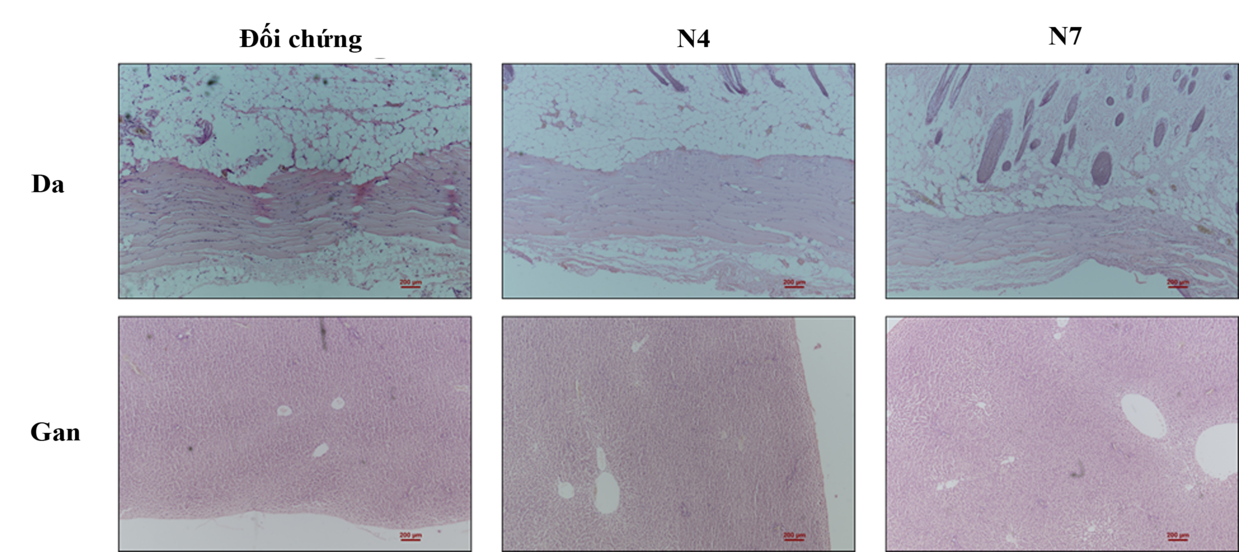

Hình 3. Mẫu mô da và mẫu gan của chuột thử nghiệm sau 30 ngày cấy ghép nẹp xương.

Mẫu đối chứng: Nẹp xương inox 316L; Mẫu N4: Nẹp xương inox 316L phủ màng đa lớp đa thành phần TiN/CrN/Ti; Mẫu N7: Nẹp xương inox 316L phủ màng đa lớp đơn thành phần TiN/Ti.